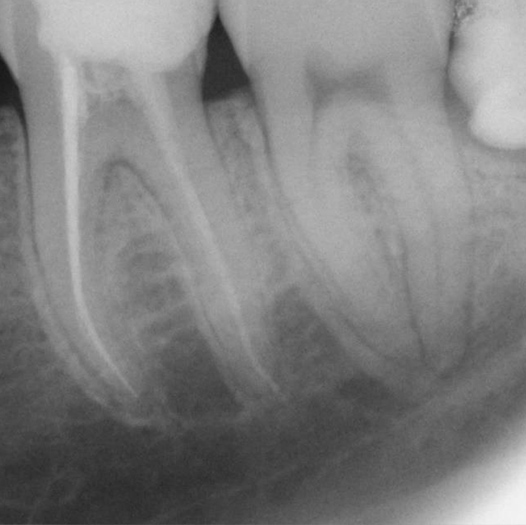

Before

Before Root Canal treatment